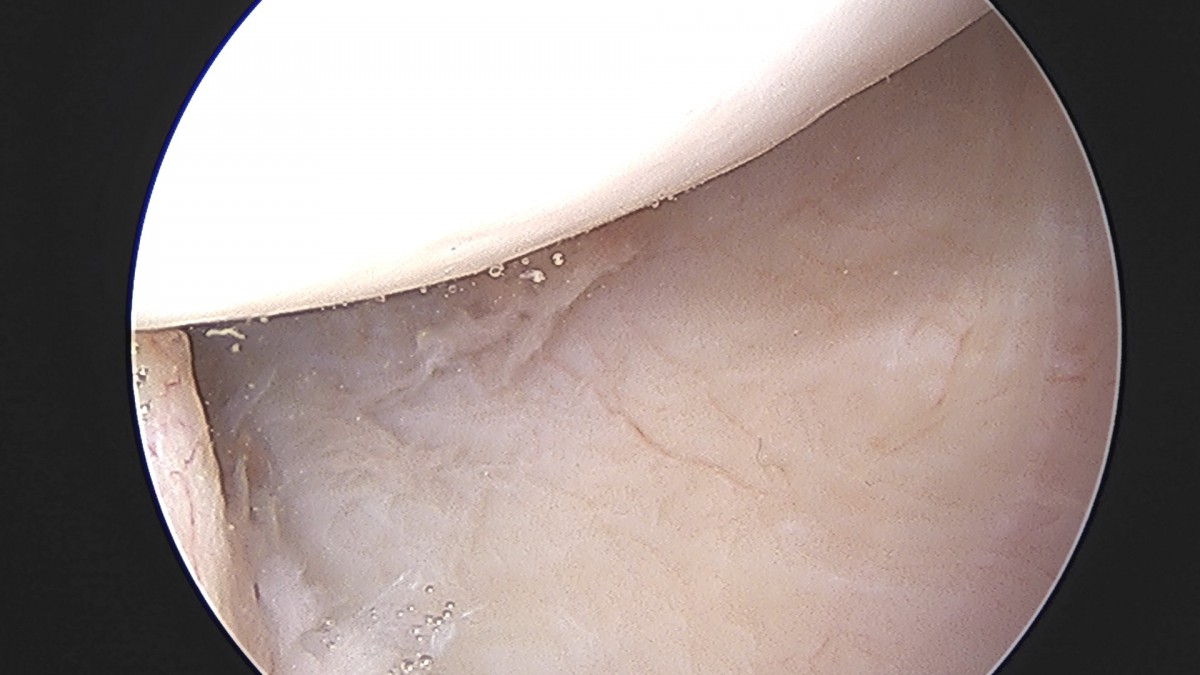

정지영원장님 어깨 회전근개 봉합술 김영O 환자

dae765e4d9ac96aee867c9d6292d8784_1758009061_6493.jpg